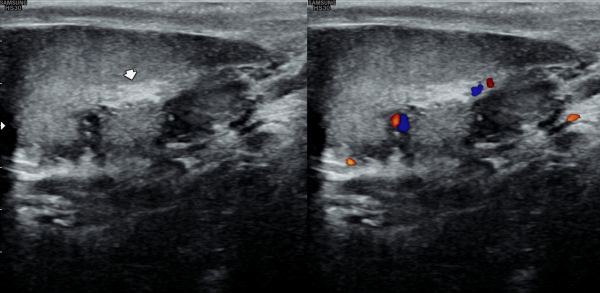

수년전부터 회음부에 통증이 있고 빈뇨가 심하다고 내원 당일 검사한 경직장 전립선 초음파 사진상 사정관의 낭종과 사정관이 좁아지고 있는 자료입니다.

A transrectal prostate ultrasound image taken on the day of the visit shows a cyst in the ejaculatory duct

and narrowing of the duct in a patient who had been experiencing perineal pain and severe urinary frequency for several years.